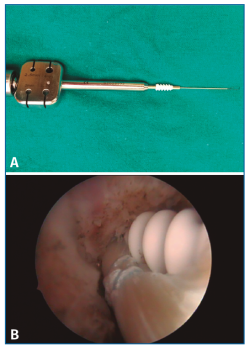

El material utilizado para esta técnica consta de: 2 tornillos de biotenodesis de 5 × 15 mm de Arthrex y artroscopio de 4,5 mm.

Para la plastia utilizamos 10 cm de extensor del 5.º dedo del mismo pie.

Con un alambre se realiza un stripping del mismo obteniéndolo fácilmente. El tendón obtenido tiene que tener un mínimo de 10 cm, lo que nos va a permitir doblar el tendón y obtener una plastia de 5 cm con el doble de grosor, unos 4-5 mm. Con una sutura realizamos un trenzado de 1,5 cm en cada extremo con el resto del hilo libre, que nos permitirá dar tensión a la misma cuando la coloquemos (Figura 4).

Figura 4. Plastia preparada de 5 cm de longitud.

A continuación, realizamos el túnel a nivel del astrágalo, desde el portal accesorio, a nivel de la inserción del LPAA en el astrágalo. Se coloca el tobillo en posición neutra y la dirección de la aguja guía es de lateral a medial, de proximal a distal, con una inclinación de 5-10° y de anterior a posterior con una inclinación de 5°. Se realiza un túnel ciego de 5 × 25 mm que nos va a permitir dar la tensión necesaria a la plastia (Figura 5).

Figura 5. Realización del túnel del astrágalo con broca canulada.